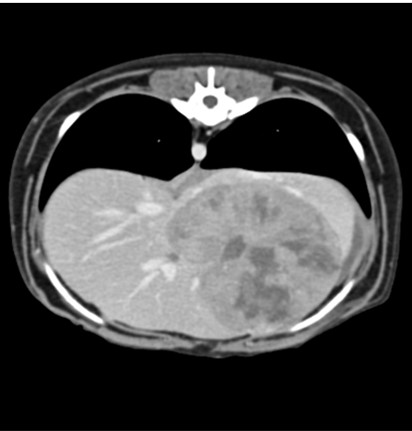

CT 검사

CT는 신체의 여러 각도에서 x-선을 투과시킨 후 단면 영상과 3차원적 입체영상을 얻을 수 있어 해부학적 구조와 병적 변화 정도를 정확하고 빠르게 평가할 수 있습니다.

CT 검사는 각종 종양과 염증, 외상 및 신체 기형과 같은 질환의 진단에 유용하게 사용될 수 있으며 수술이 지시되는 경우에도 진단을 넘어 정확한 해부학적 구조의 평가가 가능해져 이를 통해 수술 계획을 수립할 수 있습니다.

건국대학교 동물암센터에서 보유하고 있는 CT는 여러 개의 디텍터를 갖고 있는 multi-detector CT (MDCT)로써 촬영 시간 및 피폭량을 최소화 할 수 있는 장점이 있습니다. 여러 개의 디텍터를 통해 선명한 영상을 빠르게 구현해 냄으로써 진단의 정확성을 높일 수 있습니다.

대표질환

- 종양 진단 (두경부, 흉강, 복강, 사지 골격) 및 전이 평가

- 골격계 질환 및 골절 합병증 평가

- 혈관 기형 (PDA, PSS, vascular ring anomaly 등)

- 척추 질환 (척추 골절, hemivertebra)

- 폐 질환

간 종양 -

비장종양 -